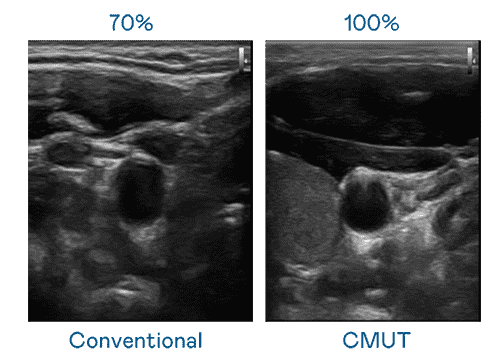

CMUT 技术是一种用电容式微机电元件来产生超音波讯号的技术。。。。与传统 PZT 压电式技术相比,,CMUT 频宽增加 30%,,,,更宽频的超音波讯号让影像解析度大幅提升,,,,是实现高影像品质医疗超音波扫描、、促进精准医疗发展的关键技术。。。。

大频宽带来超清晰影像

超音波影像的解析度高低,,,,首先取决于探头能发出的讯号频宽。。。。传奇国际 CMUT 可提供高清晰的超音波讯号,,,,提供高频宽、、高灵敏度、、、、影像纹理细节更高的超音波影像,,,协助医护人员缩短影像判读时间及利用精准的医疗影像进行诊断。。。。